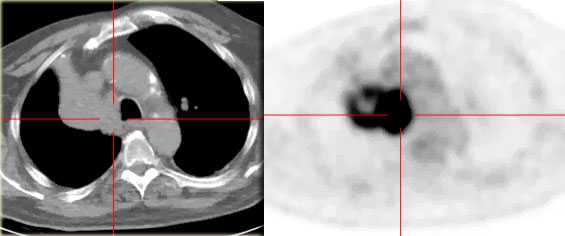

КТ органов грудной клетки. Ателектаз верхней доли правого легкого, обусловленный злокачественной опухолью правого верхнедолевого бронха

На ПЭТ/КТ визуализируется опухоль легкого с обструкцией правого верхнедолевого бронха, как следствие ателектаз верхний доли правого легкого.